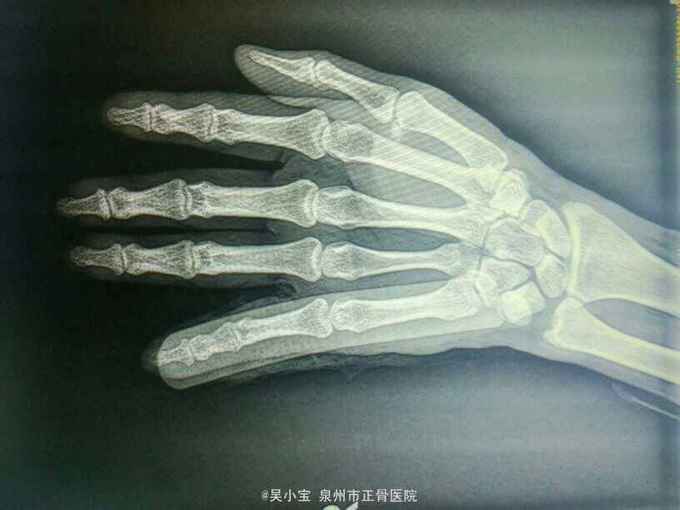

神清,舌淡红,苔薄白,脉弦。心肺腹查体未见明显阳性体征,右手第5手指部成角畸形,未见皮破出血及骨质外露,第5指近、中、远节指骨压痛,未及明显骨擦感及异常活动,左手第5手指活动受限,纵向挤压痛弱阳性,指间关节弹性固定,余各指活动正常,肢端感觉血运好,余肢体关节检查未见明显异常。 辅助检查:右小指正侧位片检查报告(检查号:DR720609,2016.01.06,本院 ) 示:右手第5指近中远节指骨重叠,并向背侧移位,呈脱位状改变;近节指骨远端掌侧缘见一小片状游离高密度影;邻近软组织肿胀。余未见特殊改变。 诊断意见:右手第5指近、远端指间关节脱位,考虑并中节指骨基底部撕脱性骨折。

诊断:1、右手第5指近节、远节指间关节脱位;2、右手第五近节指骨基底部撕脱性骨折。 治疗:手法整复铝板固定, 维持外固定制动,注意肢端感觉及血运情况,如出现肢端麻木、冰冷、变紫、外固定松动或者骨折端疼痛不适,应及时就诊并调整外固定。加强休息,患肢禁活动 2天后门诊复诊,定期复查。